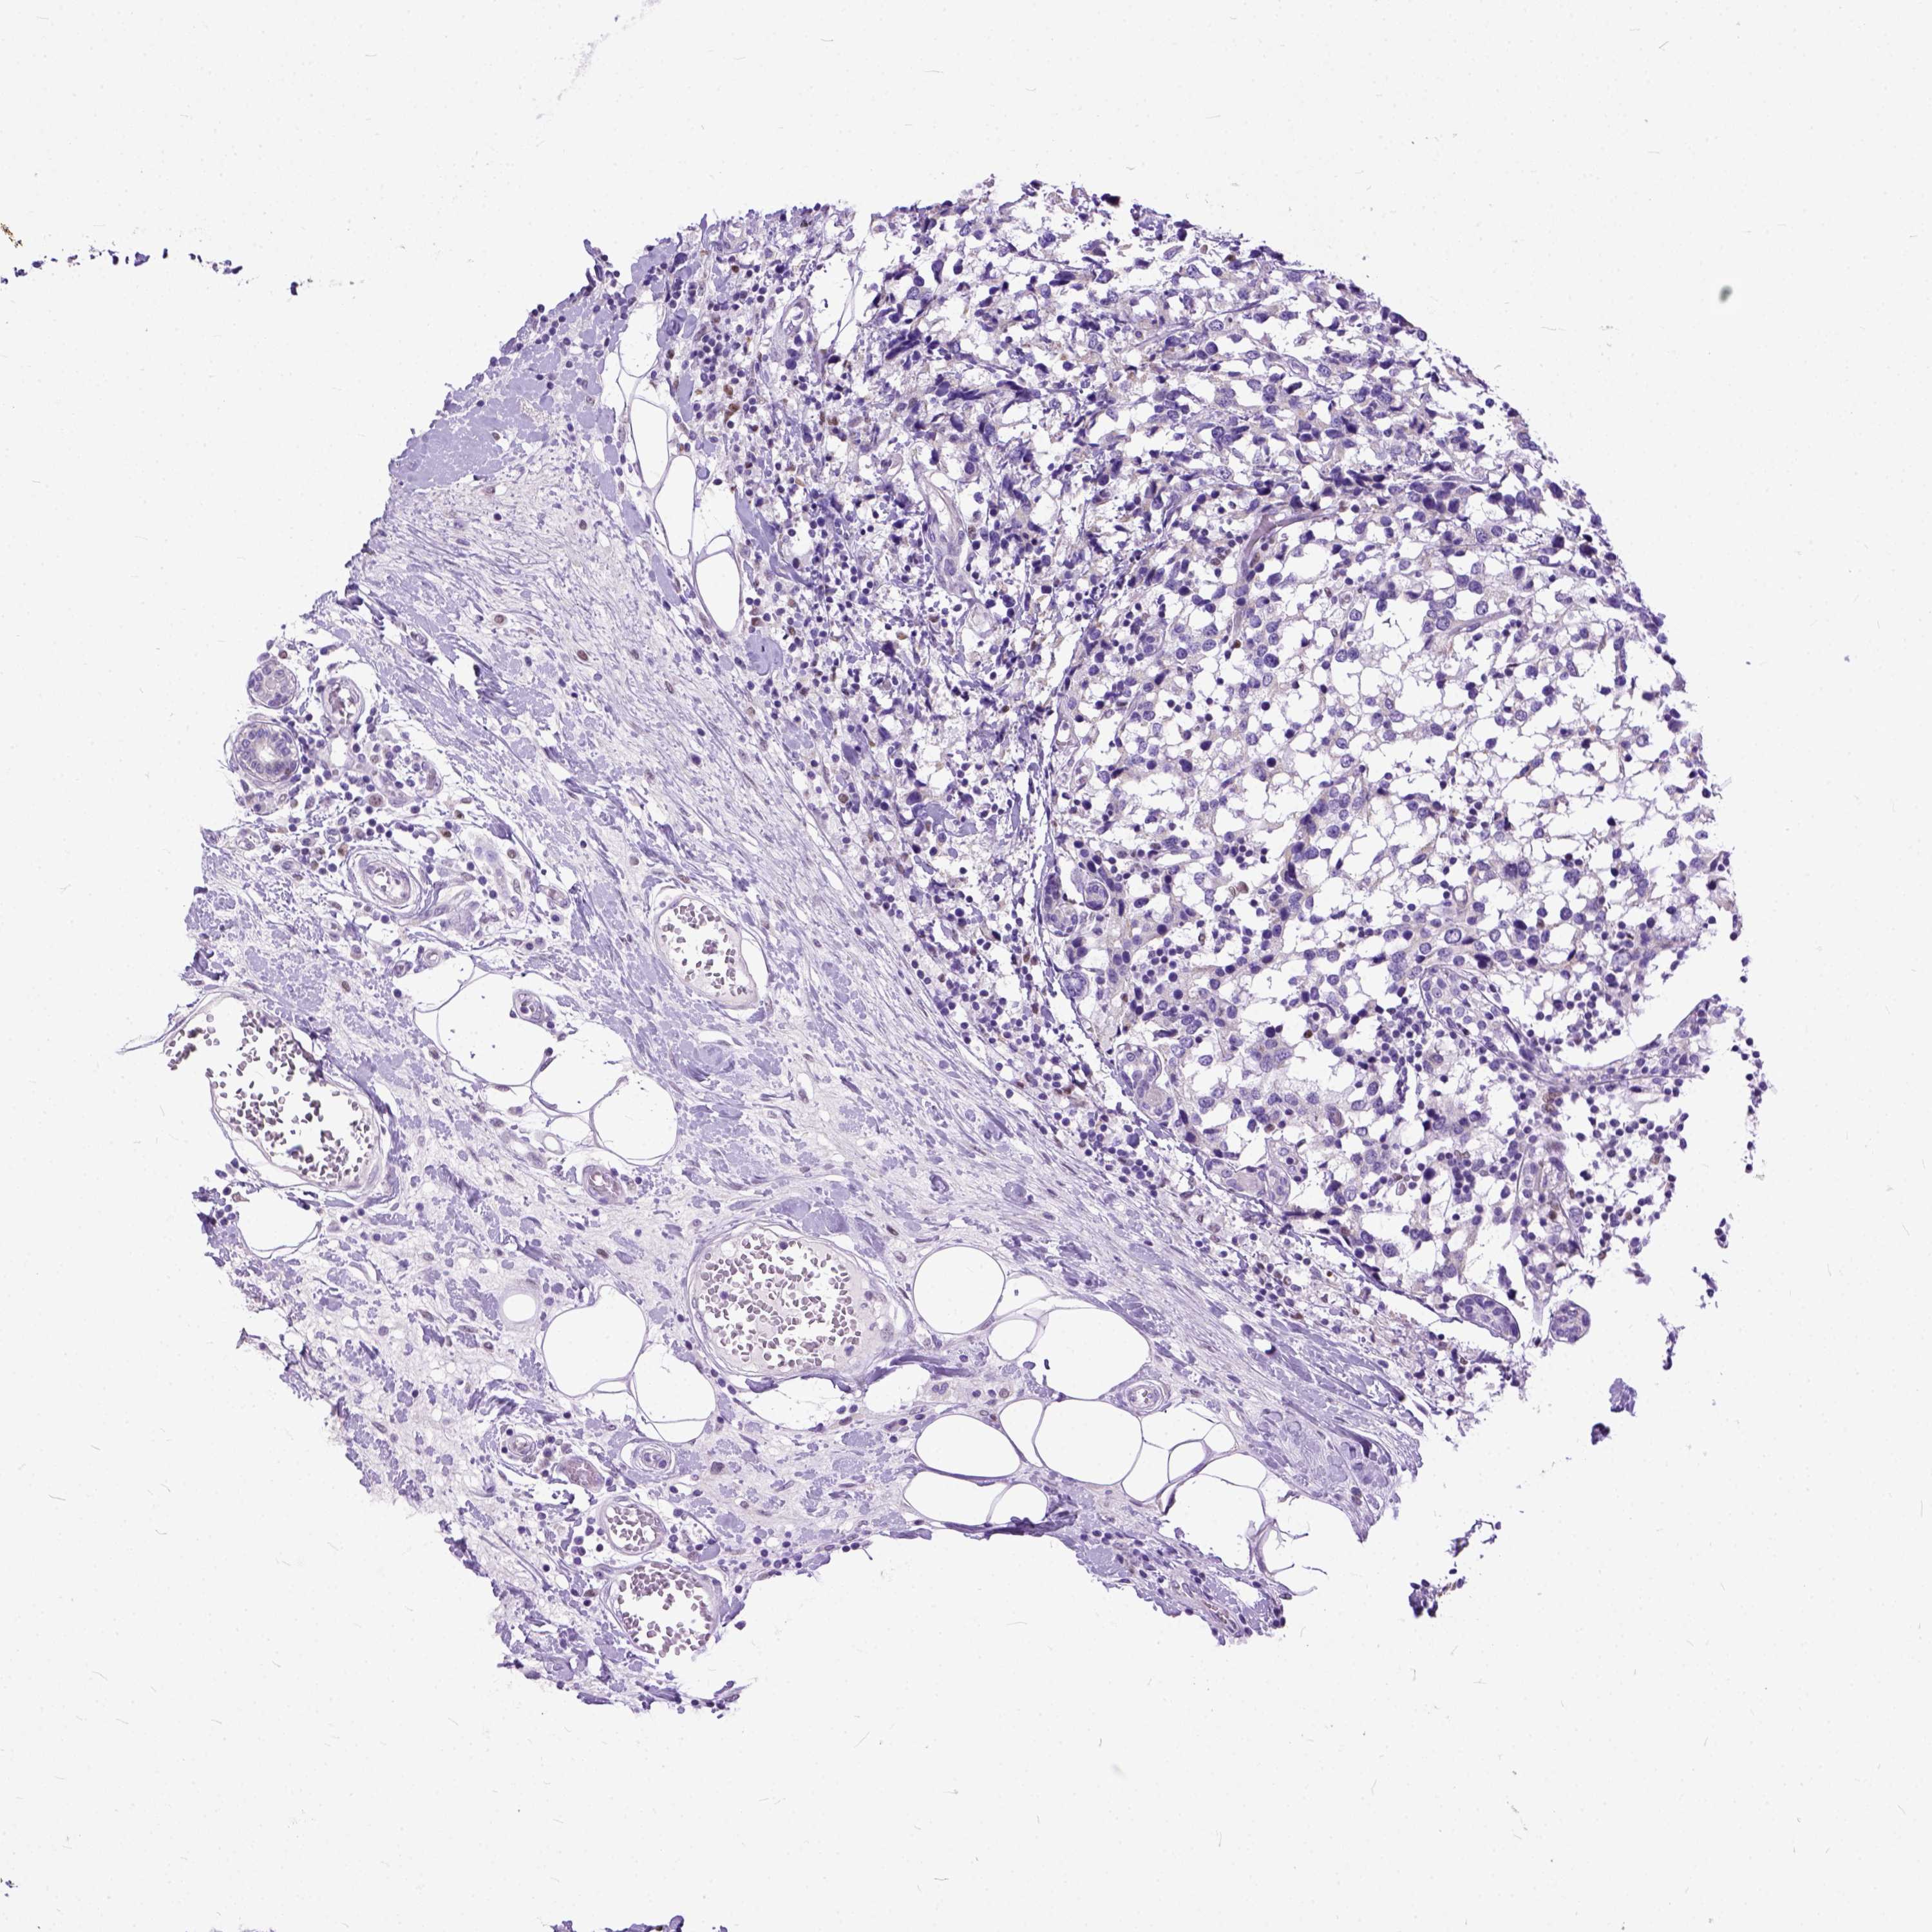

CANCER BREAST CANCER Show tissue menu

BRCA TCGA BRCA VALIDATION PROTEIN EXPRESSION